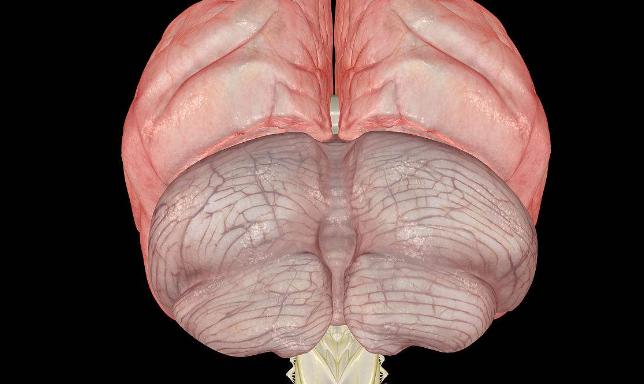

最近,从医学专业杂志《刺针》上传来一则好消息:麻省理工学院著名认知科学家斯帕克初步认定:爱因斯坦的大脑结构与其特殊功能之间存在某种内在联系。斯帕克发现,就在位于齐耳高度、从脑前延伸至后部2/3的下顶叶处,即人脑处理数学思维、三维形象和空间关系等的关键部位,“爱脑”确实与“凡脑”不同:后者的顶叶和颞叶之间通常由“西尔维裂沟”所分裂,形成一道脑上天堑;而“爱脑”的裂纹却在接近顶叶处戛然而止,并急转直上,绕过顶叶不再分裂。于是“天堑变通途”,保持了顶叶的相对完整,而且顶盖骨也模糊不见,因此整个大脑顶叶沟壑纵横,路径曲折,密密麻麻覆盖全脑,联结面积比普通人大约15%。这意味着,更多的脑细胞或神经元更易于联系,可以更好地协调工作。

关于爱因斯坦大脑“下叶区智慧”的研究也有新的发现。不久前,由加拿大麦克马斯特大学教授桑德拉,威尔特森领导的研究小组发现,位于爱因斯坦后脑左右半球的上部顶下叶区域比常人大15%,其机理非常发达。这项研究成果发表在著名医学杂志《柳叶刀》上,认为爱因斯坦的天才是天生的,并非全靠后天用功求学得来,证实后天的努力虽然也能成才,但天生天才也是事实。大脑中负责视觉思考和空间推理的顶下叶区域发达,对一个人的数学思维、想象力以及视觉空间认识都发挥着重要作用。这一研究解释了为何爱因斯坦有独特的抽象思维与过人的空间认知能力——左右半球的上部顶下叶区域比常人要大。

斯帕克指出,爱因斯坦大脑左右上部顶下叶区一般大,二者都大于常人15%,而脑重不增。有了这个完整、宽大的小叶,即可通过千百万突触所构成的微循环,容纳更丰富也更紧凑的空间与数学推理的逻辑思维线路。因此,思维敏捷、思路活跃的爱因斯坦之所以成为绝世天才,很可能是胎儿发育早期自然形成的。

特异之二:爱因斯坦大脑不仅在左右上部顶下叶区比一般人大15%,更不寻常的是顶下小叶区缺少常人都有的一条特殊的裂缝,导致两块关键的脑部区域成为一个整体。有了这个完整、宽大的小叶,即可通过千百万突触所构成的微循环,容纳更丰富也更紧凑的空间与数学推理的超凡逻辑思维缨路。

特异之五:这是迪安·法尔克在《进化神经科学前沿》上发表的最新研究成果。爱因斯坦大脑表层的很多部分没有凹沟,因此神经细胞可以通行无阻地沟通,思维也能够活跃无比。维特森指出,爱因斯坦大脑的顶叶异常发达,在形态上也有特异之处,例如侧脑裂并不明显,特别是左半球。因此顶叶下段皮质中的神经元易于相互联系,使爱因斯坦在视觉、空间认知、数学思考、运动知觉这些认知领域中,表现出超卓的智力。